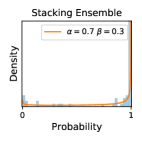

5.1 Distribution of Uncertainty Scores

Distribution of Uncertainty Scores Across Different Severity Levels As explained in Section 3, each uncertainty metric essentially defines an order/ranking among the data points. We conducted an analysis to better understand what data will be assigned high uncertainty under a particular uncertainty metric . Picking out the highest ranked data points (), we calculated the ratio of data points from each SL. Figure 4 summarizes the results as box plots for the Kaggle-DR and the Messidor-2 datasets; additional detailed statistics can be found in Table S.1 in the supplementary materials. From the plot and table, SL1 & SL2 examples account for a higher proportion among the top-ranked uncertain examples across the three ensemble methods. This finding matches our intuition that incipient disease examples (SL1 & SL2) are more likely to be considered uncertain by ensemble methods due to their ambiguity.

Comparing the three ensemble methods in Figure 4, the stacking ensemble method has the highest ratios of SL1 & SL2 data among the high-uncertainty examples it identified under both mean and var. TTA showed slightly better performance than MC-dropout but still falls behind the stacking ensemble method. Considering the fact that SL0 examples accounted for the majority of the dataset, the stacking ensemble method was much more precise (specific) in selecting truly ambiguous data points that were difficult to classify. From Figure 3, we can also see that the stacking ensemble method greatly outperformed the other two methods in finding false negatives under both mean and var uncertainty metrics.

In contrast, the MC-dropout method showed the worst overall performance among the three, as it can be seen from the high ratios of SL0 examples among the uncertain negatives in Figure 4. The histograms in Figure 2 provides another perspective to look into the phenomenon, where a decent proportion of MC-dropout model’s predictions on SL0 inputs entailed low confidence (far from 0 or 1), which from another angle explained why MC-dropout was less specific in terms of lower FNP; many no-DR inputs (i.e. SL0) were erroneously assigned high uncertainty by MC-dropout models.

It is still an open question why the evaluated MC-dropout networks signaled relatively high uncertainty on SL0 & SL3 & SL4 data that are less likely to be ambiguous. We conjecture that much of the “uncertainty” indicated by disagreement among test-time dropout samples actually reflects the stochastic nature of dropout networks rather than the real decision uncertainty associated with the data. It is worth noting that the MC-dropout model we evaluated was not weak per se; they all achieved above Area Under Curve (AUC) scores on test sets. The weakness of individual test-time samples (which explains their low-confidence predictions on SL0 & SL3 & SL4) might have been hidden when they are aggregated into an ensemble—a well-known advantage of ensemble learning. Our results suggested that the uncertainty information given by implicit ensemble methods such as MC-dropout and TTA might not be as reliable as that from explicit ensemble approaches (e.g., stacking ensembles). Similar findings on MC-dropout can be found in some previous papers [1].